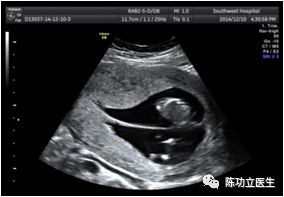

超声表现:双胎峰。超声医生如果在报告中如果能附上绒毛膜性的图,不胜感激哟。

λ征:(双绒双羊)